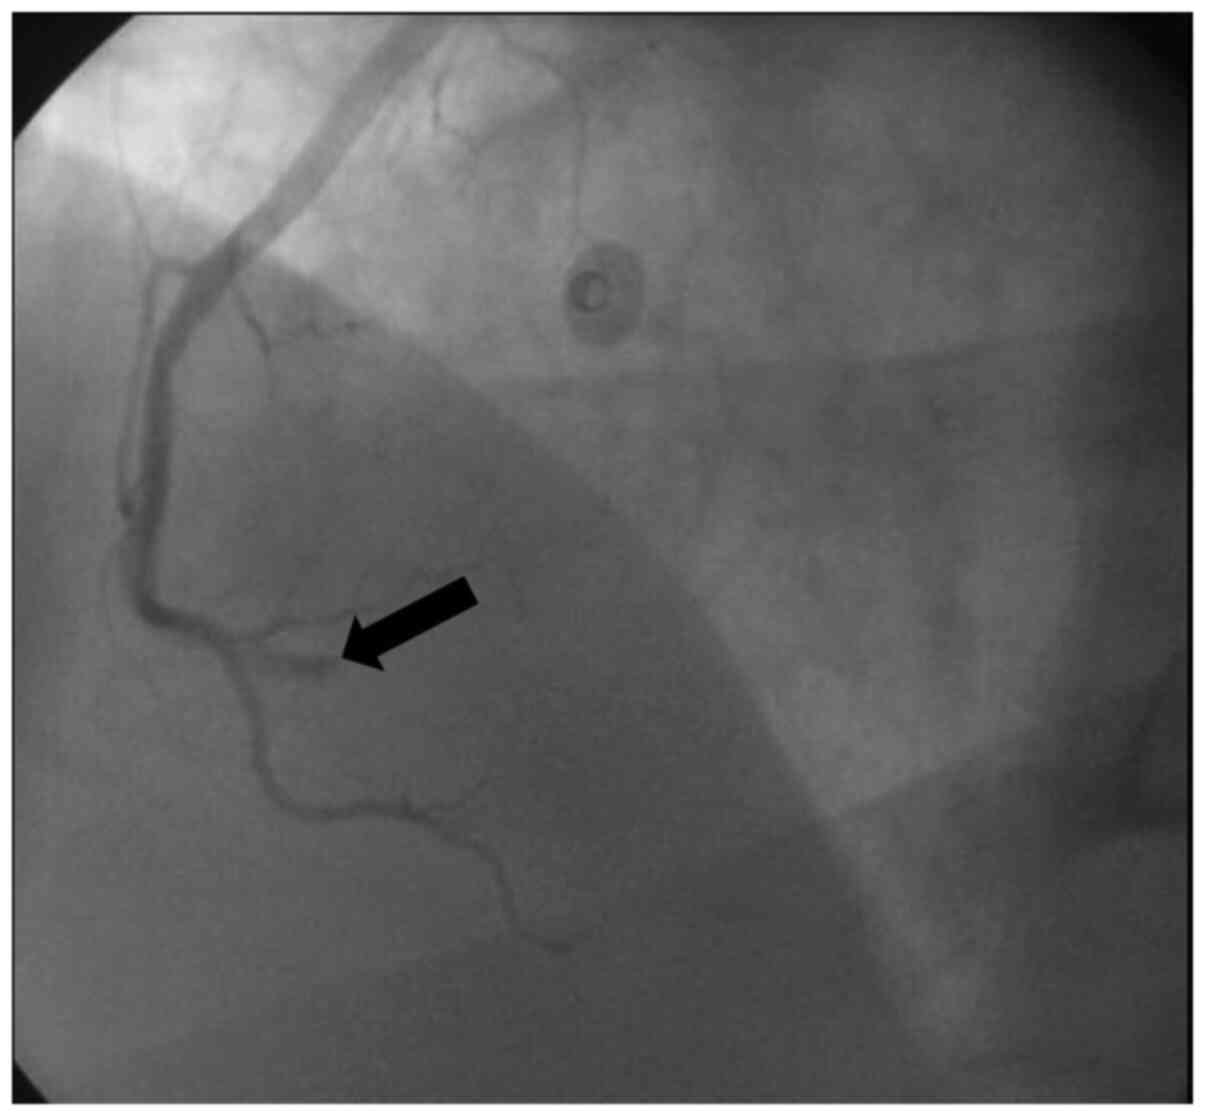

Urgent cardiac catheterization was performed 1 h after admission to the CCU, and total occlusion of the ostium of the left anterior descending artery by large thrombus was observed (Fig. 1). Successful recanalization was performed with a bare metal stent (BMS) (3.5x23 mm), and thrombolysis in myocardial infarction 2 flow was established. The patient was then administered tirofiban using percutaneous coronary intervention (PCI). The left circumflex artery was normal; however, notably, the right coronary artery (RCA) was affected: The pre-bifurcation was totally occluded by an embolized thrombus (Fig. 2). This may explain the changes in ECG observed in the CCU. Successful recanalization was performed with a BMS (3x18 mm). An intra-aortic balloon pump was inserted, and the patient was administered a small dose (5 µg/kg/min) of the vasopressor dopamine for 2 days.

Figure 2

Angiogram of the right coronary branches. The black arrow indicates the area of the right coronary artery affected. The pre-bifurcation was totally occluded by embolized thrombus.

Notably, in the present case, the patient may have suffered from both atherogenic (Fig. 1) and thrombotic (Fig. 2) coronary blockages. However, as it was not possible to examine the patient prior to hospital admission, it is unknown if the use of AASs caused the left atherosclerotic coronary lesion or, alternatively, if this use exacerbated a pre-existing lesion. Conversely, there was no clear evidence of an intra-ventricular thrombus, which may have explained the embolic thrombus in the right coronary artery. The documented evidence of the ability of AASs to increase blood thrombosis (5) may explain this event. In addition, although the vasospastic mechanism is less established as a factor in AASs-based AMI (15,16), it may possibly intensify the atherogenic or the thrombotic mechanisms of AMI in AASs users. In concordance with these data, AAS abuse has been identified to induce vascular and endothelial dysfunctions (17,18). Therefore, vasospastic agents were added to the pharmacological regimen of the patient in the present report. In addition, the ability of chronic AASs use to cause arrhythmias (19,20) may lead to spontaneous formation of small thrombotic embolisms, which in turn, may be transported toward the coronary arteries and cause significant blockages. Notably, the AMI itself in chronic AASs users may also cause disruption to the autonomic nervous supply of the heart, which may predispose these individuals to spontaneous arrhythmias (5,21). In turn, this may cause a thrombotic event within the ventricles, which may translocate to the coronary arteries and cause an embolism.